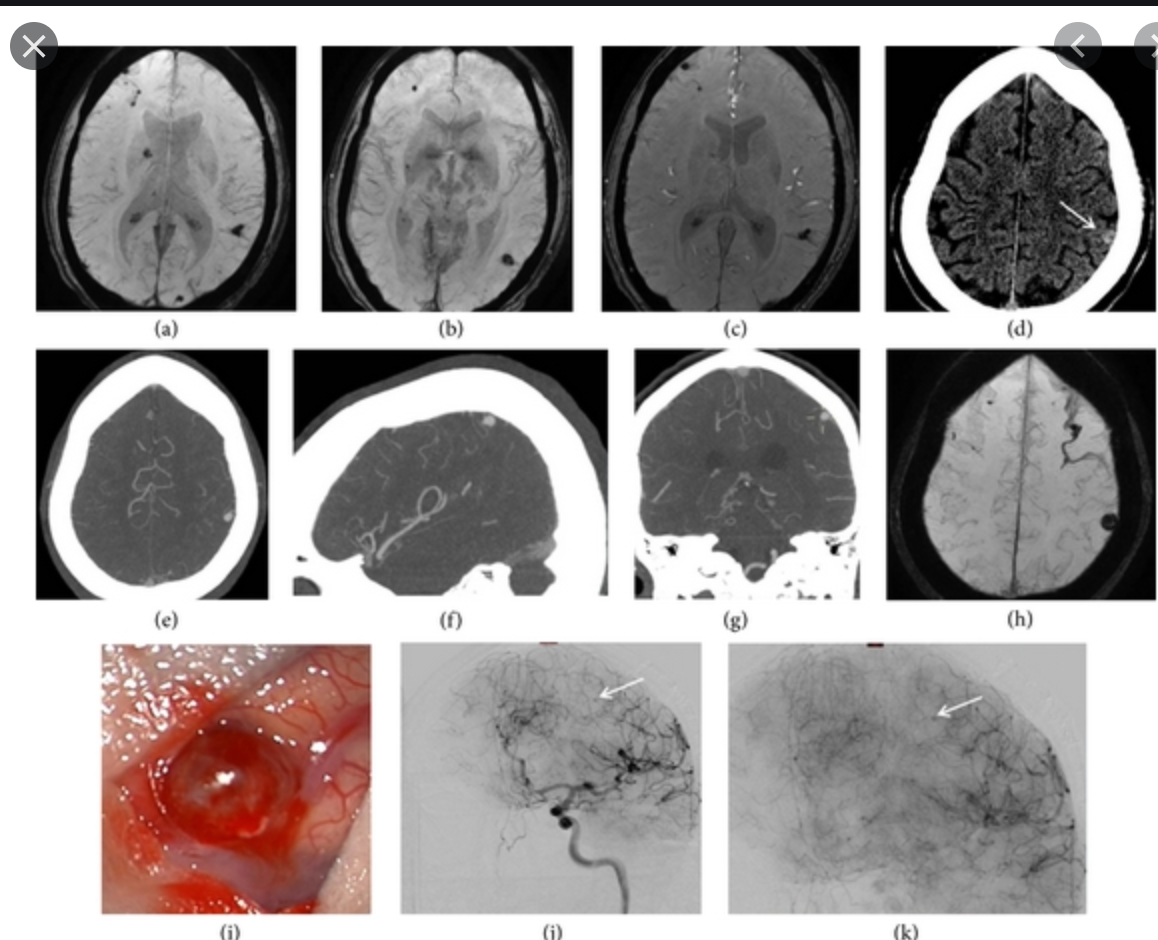

Imaging features of Vein of Galen AVM

Vein of Galen aneurysmal malformation

Vein of Galen aneurysmal malformations (VGAMs), probably better termed as median prosencephalic arteriovenous fistulas, are uncommon intracranial anomalies that tend to present dramatically during early childhood with features of a left-to-right shunt and high-output cardiac failure.

Radiographic features

Antenatal ultrasound

With increased availability and quality of antenatal ultrasound, the diagnosis is increasingly made prior to delivery. Antenatal detection is however mostly reported late in pregnancy (3rd trimester).

The dilated median prosencephalic vein (MPV) appears as an anechoic structure in the midline posteriorly and demonstrates prominent flow on Doppler examination. Shunting may lead to complications such as hydrops fetalis or fetal cardiomegaly.

CT and MRI

Both CT and MRI can be used to delineate the malformation cross-sectionally.

CT angiography

CTA in neonates with high output cardiac failure is technically-challenging due to the small volumes of contrast and very rapid passage of contrast through the circulation.

MR angiography

The dilated feeding and draining vessels appear as flow-voids on T2. MRA may also be performed which would better delineate vascular anatomy.

Angiography

Angiography remains the gold standard in full characterisation of the lesion. It enables to individually catheterise feeding vessels. Morphologically a spherical or ellipsoid varix may be visualised. Venous drainage is via the median prosencephalic vein (MPV), the straight sinus (if present) and then out via the transverse/sigmoid sinuses. By definition, there should be no drainage to other components of the deep venous system 6.